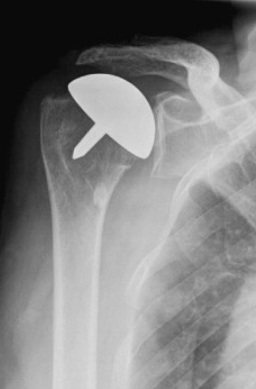

A partial shoulder replacement involving the replacement of only the surface of the ball or the humeral head with an artificial cap without the stem. This is an alternative to the stemmed hemiarthroplasty allowing for more bone preservation.

After surgery, you will recover in the hospital for 1 or more days, depending on your individual health conditions and needs. An X-ray will be obtained and your shoulder will be immobilised in a sling. Physiotherapy rehabilitation will begin almost immediately following the surgical procedure. The initial goals of treatment are to reduce swelling and pain, while restoring passive motion. Subsequently, the treatment goals shift to active motion, strengthening the shoulder and increased functionality of the affected arm. A tailored, well planned rehabilitation program is essential for the success of a shoulder replacement in the hospital and while recovering at home.

Choosing the right hand therapist starts with them being able to read your X-rays and then fabricate the right brace for you. The therapists at Action Rehab are experienced in assessing and reading X-rays.